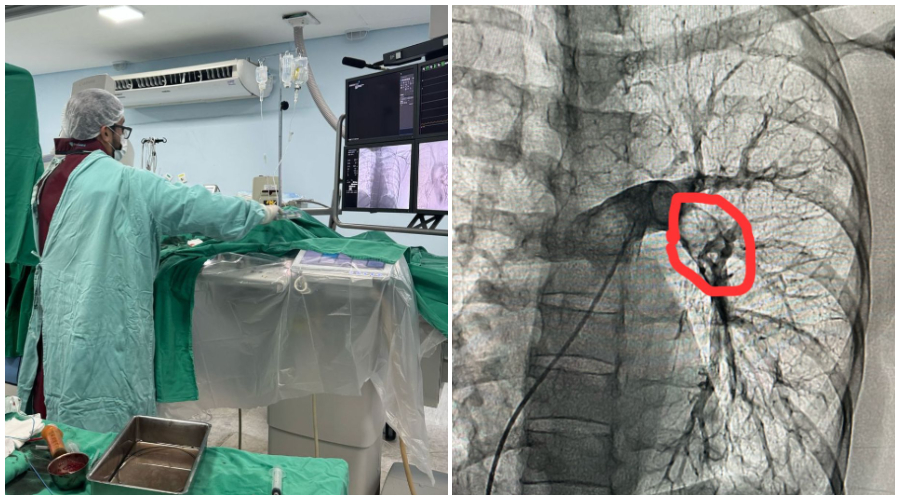

No último sábado, dia 22 de março de 2025, foi realizado mais um procedimento importante na hemodinâmica do Hospital Regional de Patos. Procedimento esse chamado Trombectomia Mecânica Pulmonar, que consiste na retirada mecânica de um grande trombo sanguíneo (coágulo) de dentro da artéria pulmonar (vaso que leva sangue para o pulmão).

O procedimento foi realizado em uma paciente de 50 anos, procedente de Patos-PB, que tinha sido recentemente submetida a uma cirurgia ginecológica, tendo evoluído com quadro de trombose pulmonar.

O procedimento foi realizado com sucesso, com a retirada pela hemodinâmica de grande quantidade da carga trombótica através da aspiração local do coágulo, melhorando assim o quadro clínico da paciente e diminuindo as pressões no leito pulmonar.

O procedimento foi realizado pelo médico cardiologista e hemodinamicista Dr. Jeann Santiago, que frisou a grande importância do tratamento: “Com esse tratamento disponível para a população sertaneja através da hemodinâmica, podemos ajudar pessoas que iriam ter um desfecho muito desfavorável e, assim, contribuir com sua qualidade de vida e prevenir até mesmo o óbito. Com certeza salvamos mais uma vida com a Trombectomia Mecânica. Me sinto muito feliz com isso”, disse.